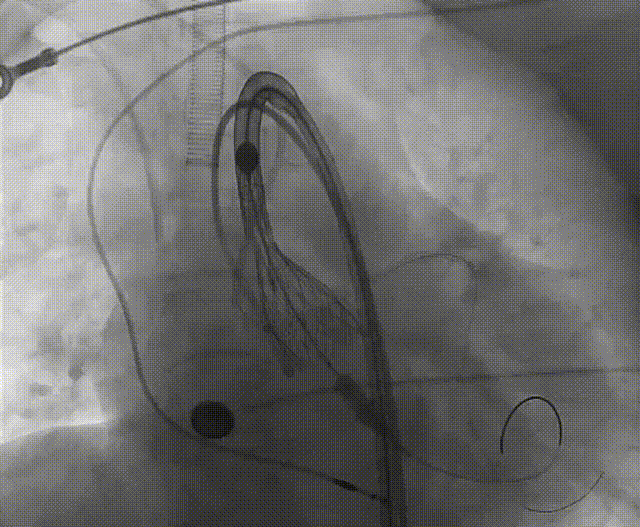

手术流程概括

根部造影

左冠脉提前植入延长导管,预埋冠脉导丝。

20mm球囊预扩张,无腰征,无造影剂泄露。

vitaflow tav24瓣膜轻松过弓初始定位瓣环0位开始释放,班第一次释放瓣膜在转移到瓣上,综合决定回收采取第二次瓣膜释放。

第二次精准零位释放,决定完全释放。

释放后多体位观察造影,瓣膜位置良好,展开良好,轻微瓣周漏。